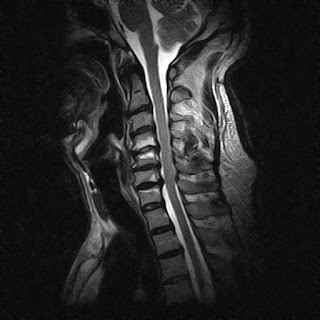

上の画像は、私の首のMRI画像です・・・画像中の首の骨の中にある2本の白い線が、かなり圧迫されて細くなっているのがわかると思います・・・

いろいろと検査をした結果、かなり重度の頸椎脊柱管狭窄症であることは間違いないものの、狭窄症による神経圧迫の場所と、手の握力低下は関係ない・・・とのことで、緊急的に手術をする必要はなさそう・・・とのことでした・・・